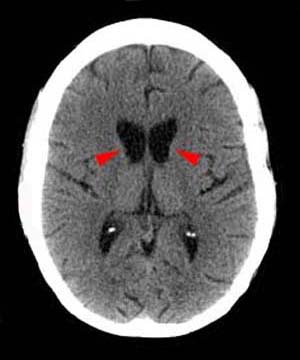

Radiographically Huntington's disease characteristically exhibits caudate atrophy on imaging. This may be manifested by a decrease in the convexity of the heads of the caudate bilaterally or by an increase in the relative volume of the lateral ventricles as seen on CT or T1-weighted coronal MR. To a lesser extent putaminal atrophy may also be manifested.

One method of referencing the degree of caudate atrophy is to use the ratio between intercaudate distance and calvarial width. Known as the bicaudate ratio, the value is found by measuring the minimum distance between the caudate indentations of the frontal horns and the distance between the inner tables of the skull along the same line and multiplying that figure by 100. The Bicaudate Index (BCI) provides a standard by which configured values may be compared to age-matched controls. This parameter has been found to correlate well with caudate atrophy.

![]() ![]() The images above are axial Head CT scans.